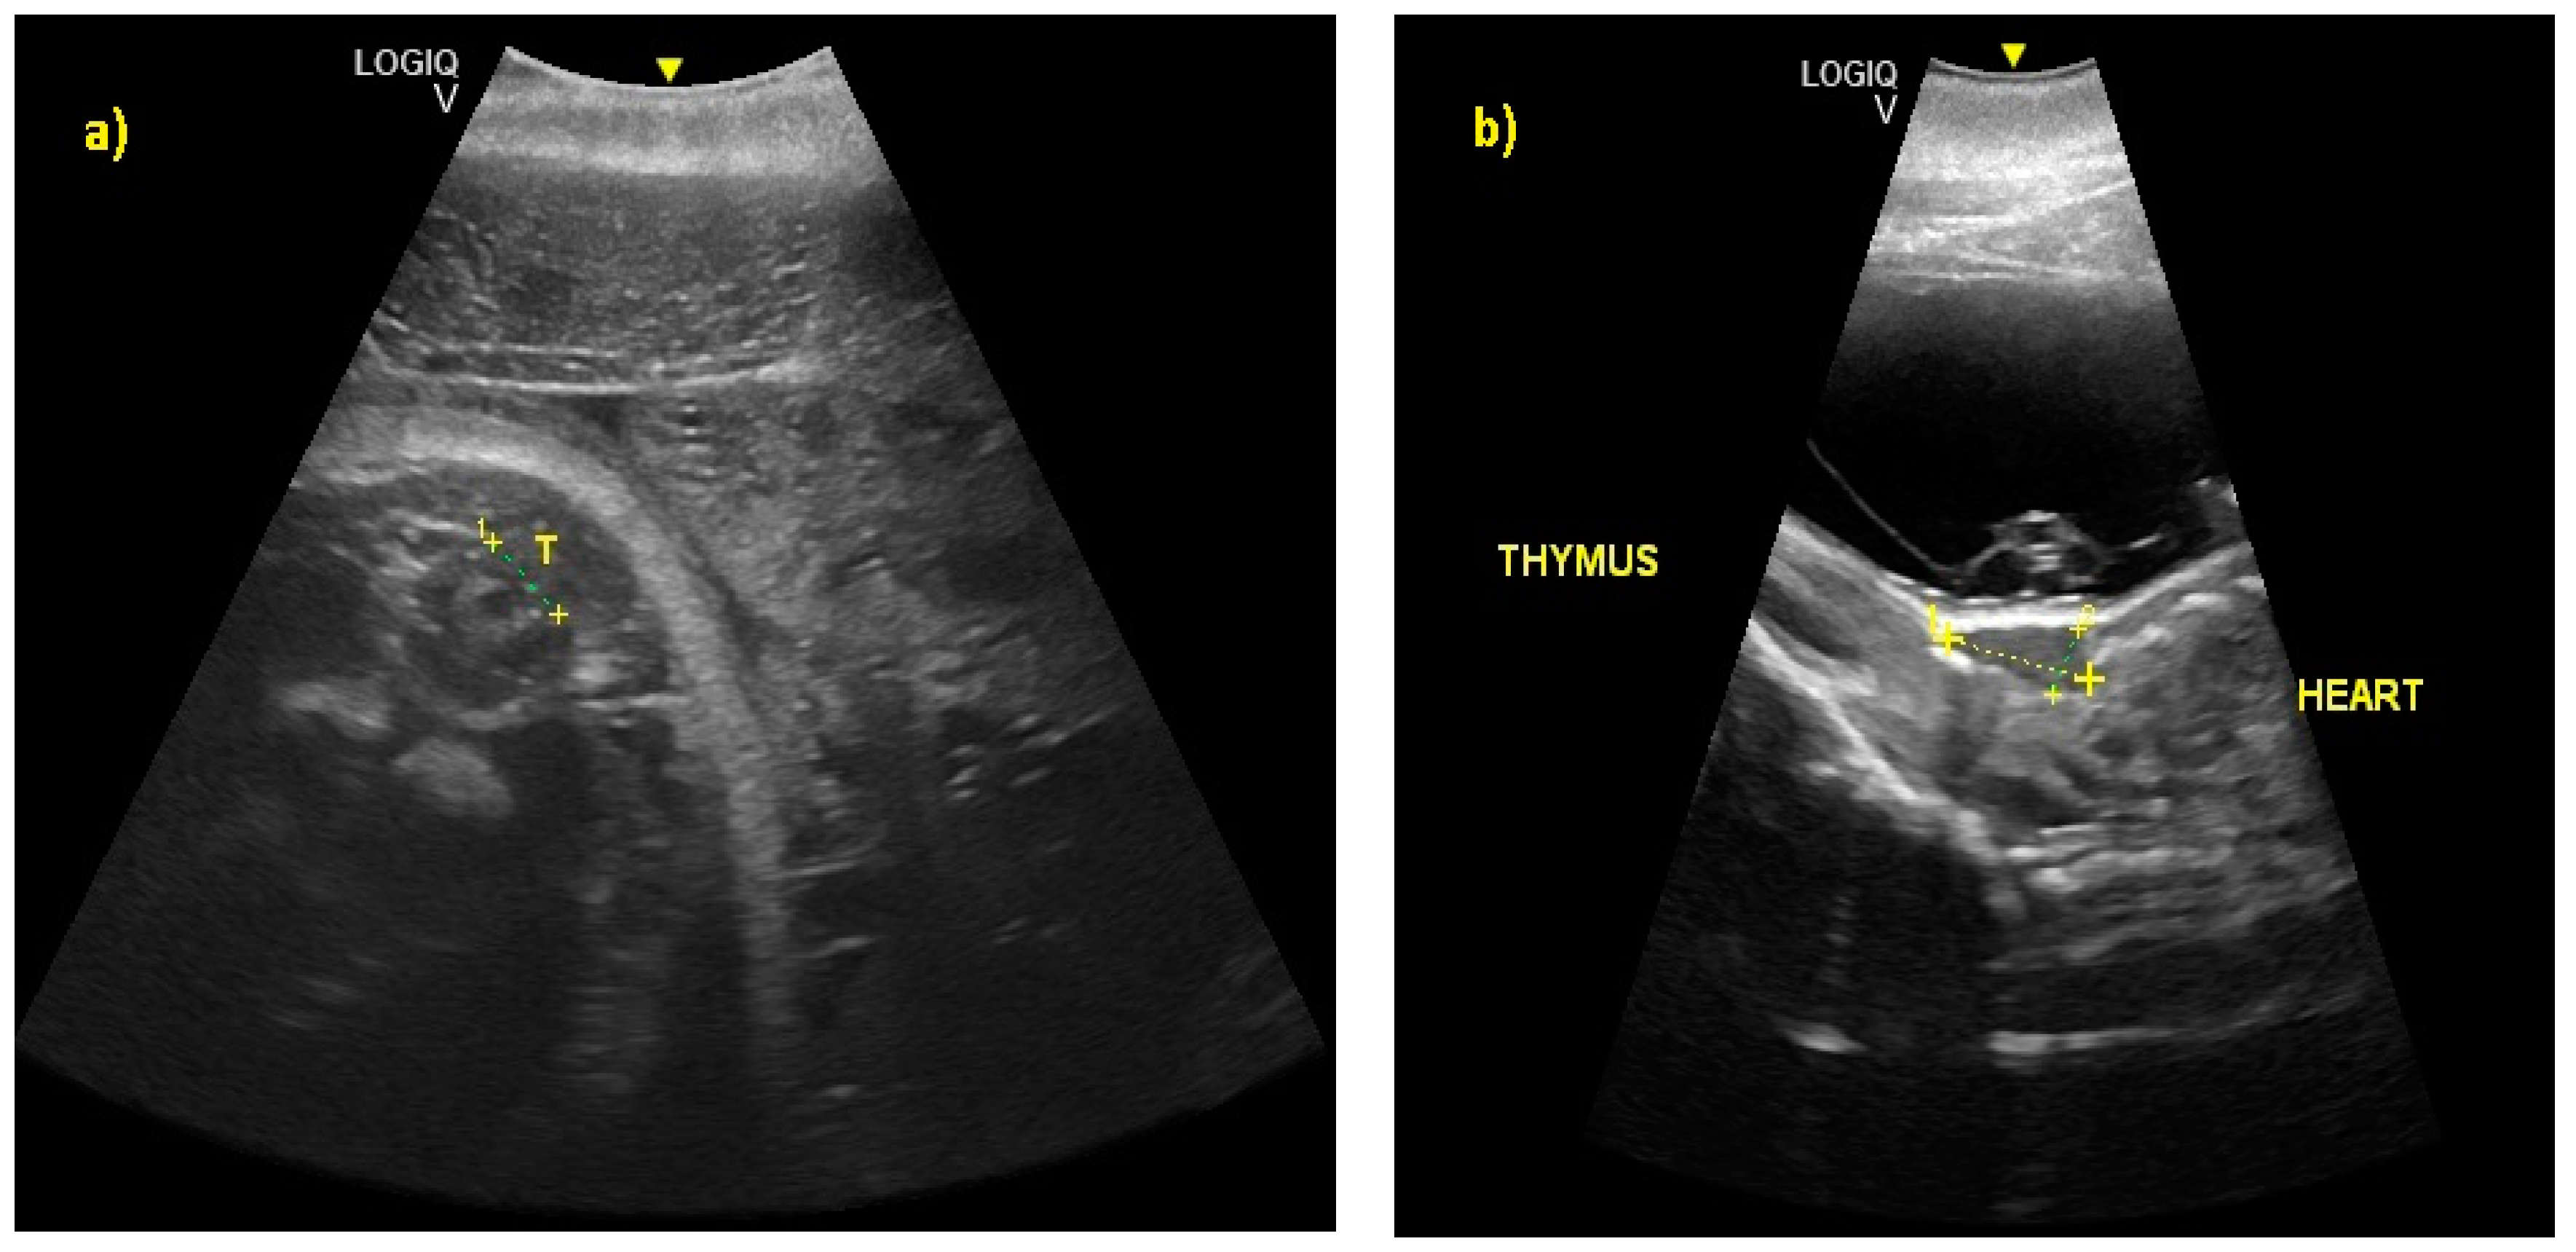

From the 230th day of gestation, it was possible to observe a ventral flexion of the caudal fin, a hyper-echoic structure, in contact with the abdomen. From the 245th to the 288th day of gestation, it was possible to recognize the thyroid and thymus (Figure 8). During the last 3 months of gestation, it was possible to identify the kidneys.

Figure 8.

(a) At 245 ± 2 to 288 ± 2 days of gestation, it was possible to recognize the thyroid (T) and (b) the thymus, respectively.